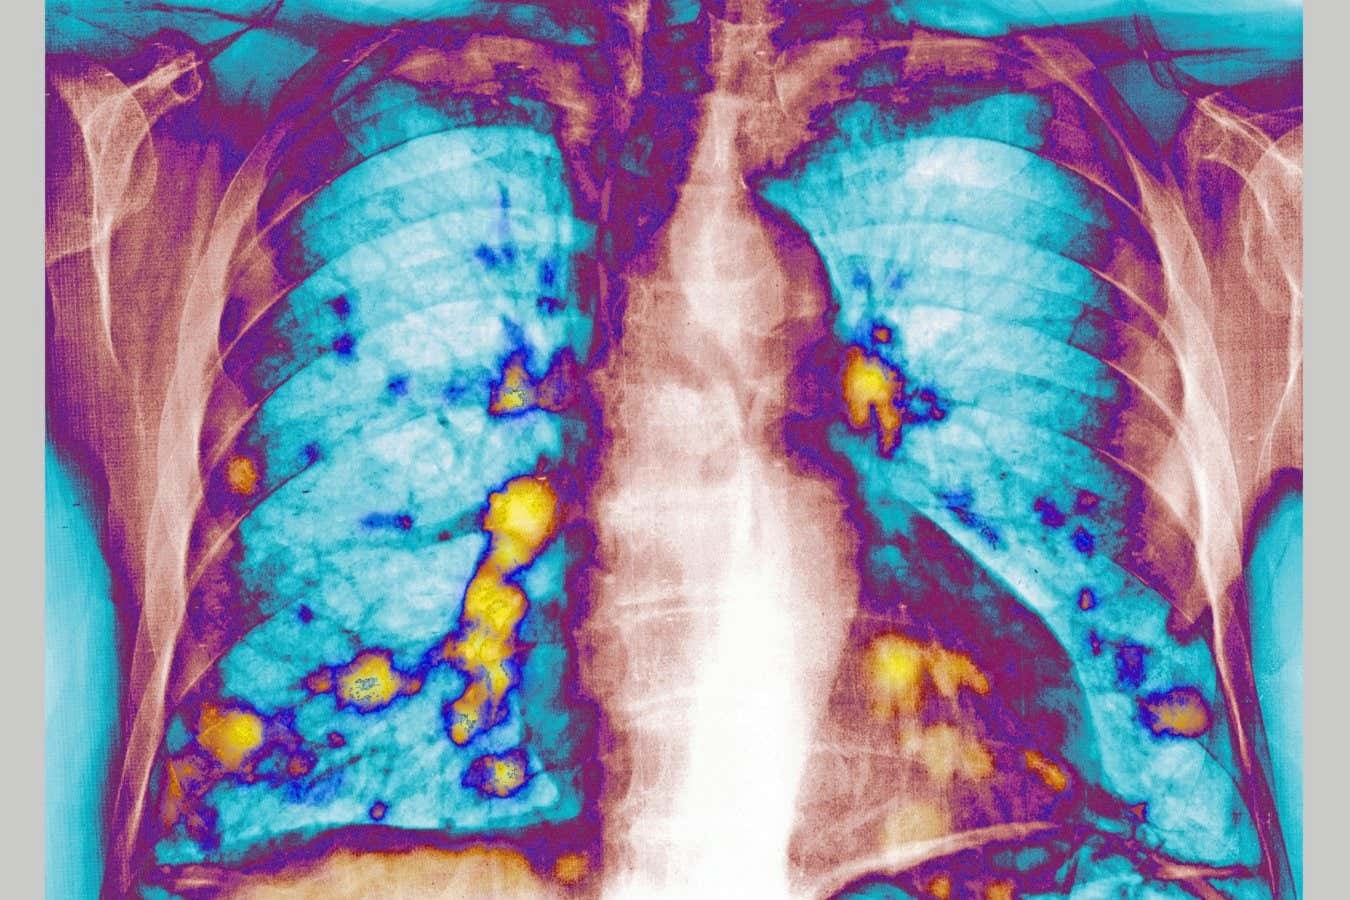

Легкі є найчастішою мішенню для метастатичних клітин. Це спонукало вчених дослідити, чи середовище грає в легенях — особливо під час вірусних інфекцій, таких як грип, COVID-19 або звичайна застуда — роль у тому, як ракові клітини «укорінюються».

3. Спостереження: Через 28 днів результати виявилися разючими. У мишей, раніше інфікованих РСВ, у легенях виявилося на 65–70% менше пухлинних вузлів порівняно з контрольною групою.